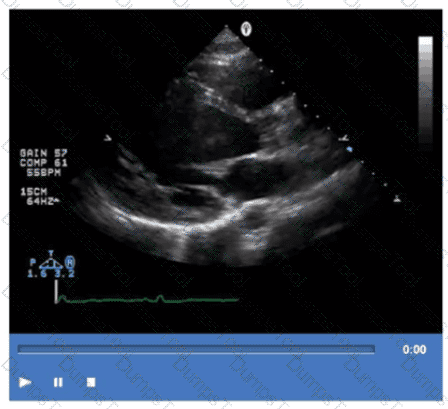

Which step is next in further evaluation of the abnormality shown in this video?